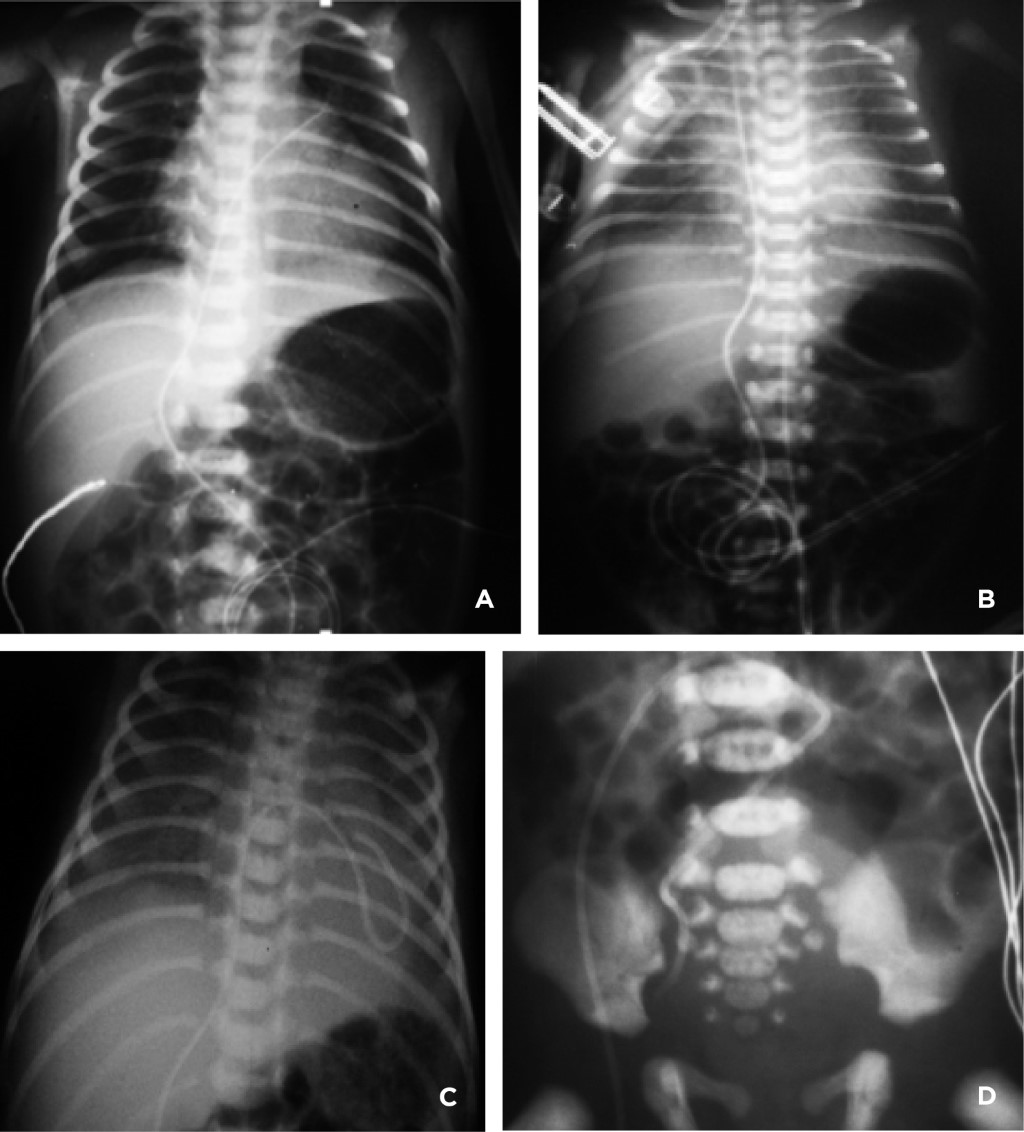

• 1. Posición anómala: provoca complicaciones relativamente menores y otras potencialmente mortales. En muchas ocasiones es necesario solicitar otras proyecciones radiológicas para tener una interpretación correcta. Ante la duda, pedir apoyo a personal con mayor experiencia o a un experto radiólogo. El catéter umbilical venoso puede quedar enrollado en cualquiera de las cámaras del corazón e incluso por arriba de él (vena cava superior, vena yugular interna, vena innominada, venas pulmonares derechas o izquierdas, arteria pulmonar), o por debajo del hemidiafragma derecho (en el sistema venoso umbilical o en vena cava inferior) (Figura 14).

• Cuando el catéter arterial umbilical queda mal posicionado, en una arteria periférica, puede provocar fenómenos por blanqueamiento de extremidades o perforación del vaso arterial. En las Figuras 15 y 16 se observa a un recién nacido con lesiones de hiperemia, necrosis y celulitis en la región glútea izquierda, por un catéter arterial mal posicionado y por el cual se infundió por error NPT, en la arteria glútea superior izquierda que perforó el vaso, al retirar el catéter las lesiones remitieron.

Figura 14

Figura 15

Figura 16